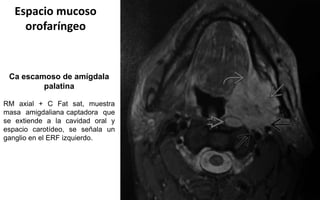

Espacio mucoso

orofaríngeo

Ca escamoso de amígdala

palatina

RM axial + C Fat sat, muestra

masa amigdaliana captadora que

se extiende a la cavidad oral y

espacio carotídeo, se señala un

ganglio en el ERF izquierdo.